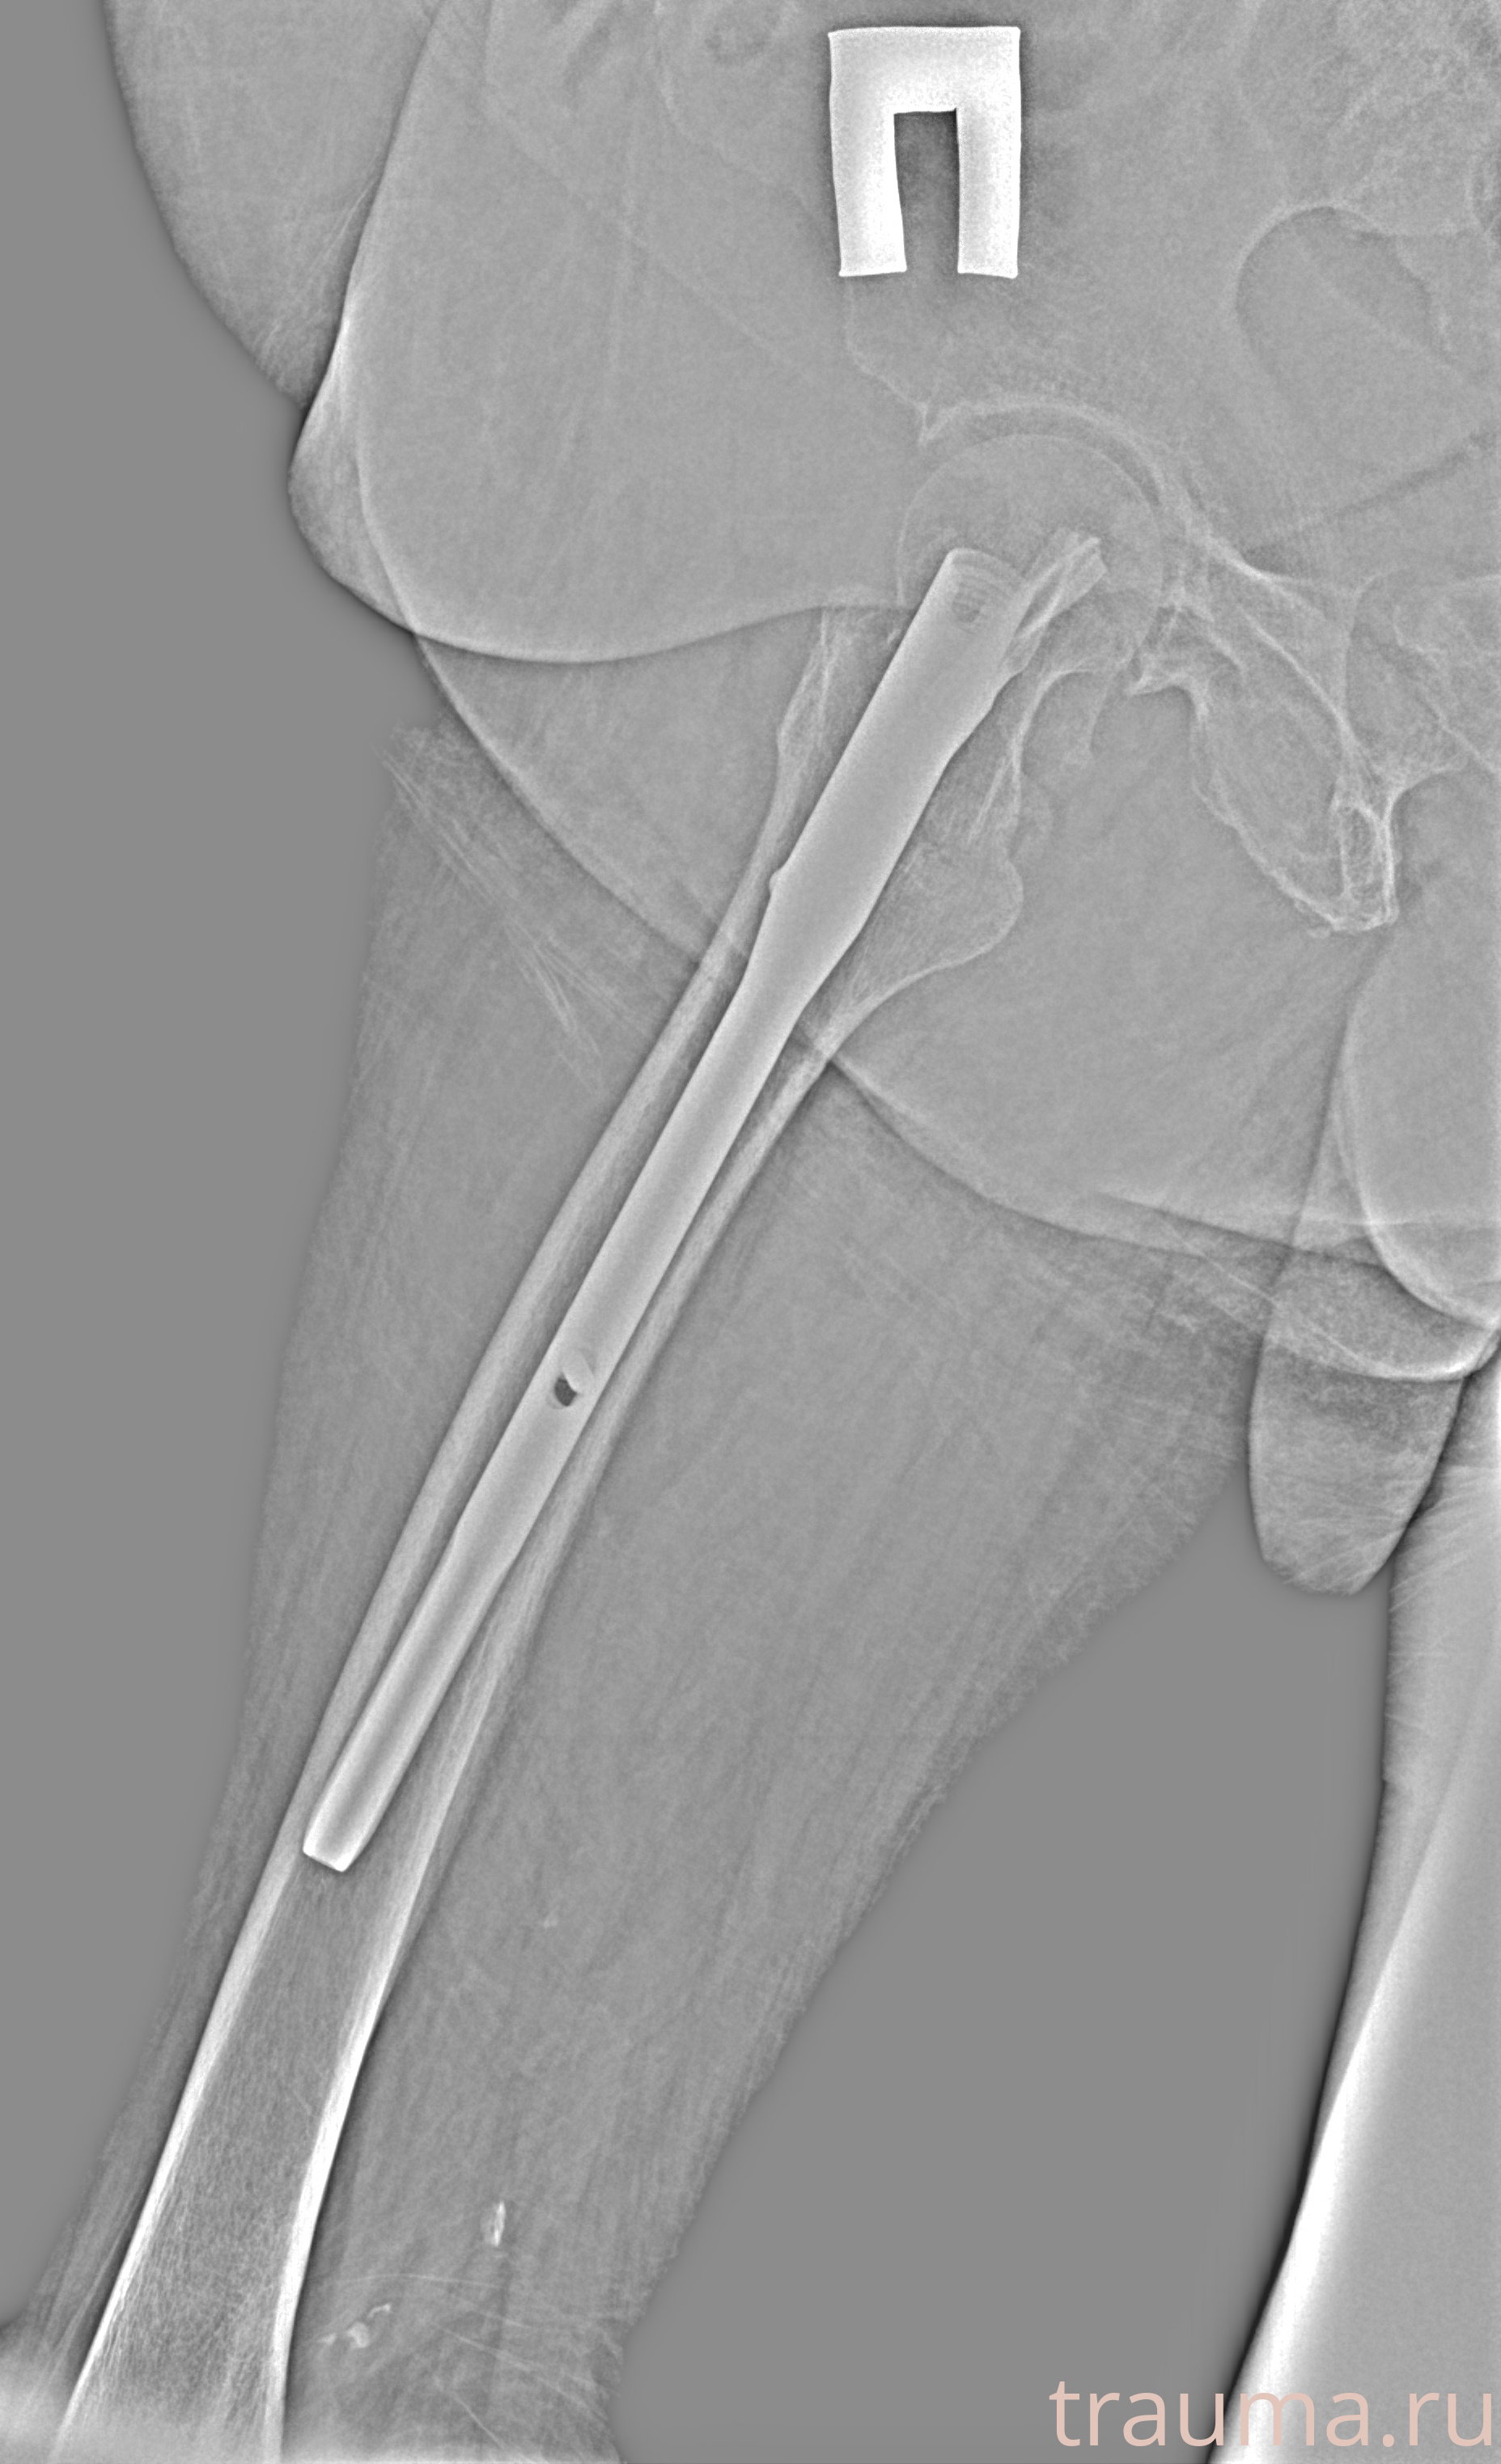

Рентген на дому: по вашему адресу приезжает врач-рентгенолог, травматолог-ортопед с мобильным рентгеновским аппаратом, проводит диагностику травмы или заболевания, делает необходимые рентгенограммы, дает рекомендации по дальнейшему лечению. Получить качественные снимки в домашних условиях возможно благодаря уникальной методике, разработанной МосРентген Центром для института  Склифосовского